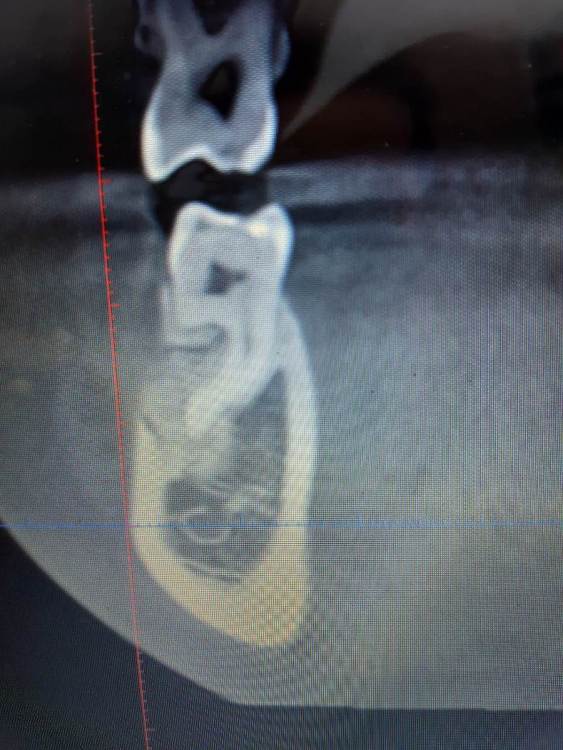

It'sGeorgy Опубликовано 15 мая, 2021 Автор Поделиться Опубликовано 15 мая, 2021 Пациент пропал на год, позвонил в клинику сегодня, отправили на кт. Сказал, на десне какой-то прыщик на десне(скорее всего, причина в этой оставленной штуки в десне) и что-то где-то там болит(сверху пульпит прям над винтом). В прошлых сообщениях забыл указать: графта не было. А вот имплантат откровенно неудачно поставил, надеюсь, десна вывезет. Да и сам имплантат, если бы сейчас ставил, выбрал Штрауманн ТЛ. 1 Ссылка на комментарий

It'sGeorgy Опубликовано 15 мая, 2021 Автор Поделиться Опубликовано 15 мая, 2021 Только что, Irouil сказал: А что,собственно, не нравится? ну язычнее надо бы...вестибулярная стенка у шейки совсем тонкая. Ну и десны после транспа с бугра много вышло, 5.5 мм по КТ(знаю, что это не всегда соответствует реальности, но все же). В таких случаях стараюсь полированной шейкой поддесневую часть выполнять, ибо любая недополировка абатмента или поддесневой части коронки будет критична. Ссылка на комментарий

Irouil Опубликовано 16 мая, 2021 Поделиться Опубликовано 16 мая, 2021 У вас по КТ и над зубами десны по пару мм. да и ничего плохого в 5 мм не было бы. Во первых, всегда можно использовать абатменты с высокой шейкой, а во вторых очень редко когда нельзя все это расформировать в широкий контур прорезывания временной коронкой. С костью все нормально, имхо 1 Ссылка на комментарий

It'sGeorgy Опубликовано 16 мая, 2021 Автор Поделиться Опубликовано 16 мая, 2021 6 часов назад, Irouil сказал: У вас по КТ и над зубами десны по пару мм. Таки да, не заметил посмотрим на этапе фдм что там с десной в итоге. 6 часов назад, Irouil сказал: а во вторых очень редко когда нельзя все это расформировать в широкий контур прорезывания временной коронкой. Обсудим этот момент с ортопедом, спасибо. Ссылка на комментарий